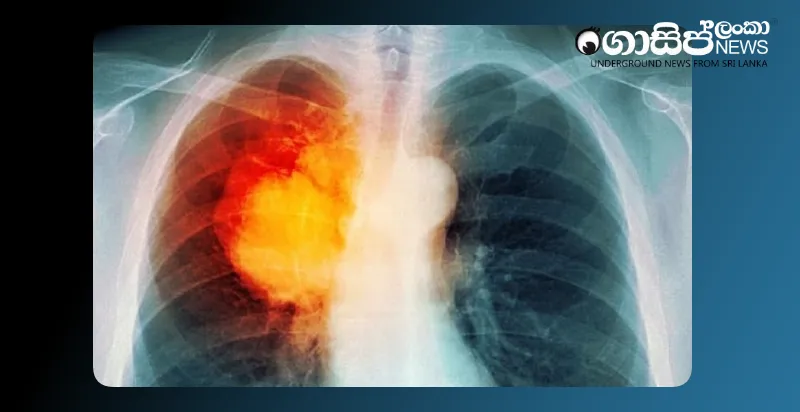

ශ්රී ලංකාවේ පිරිමින් අතර දෙවනුවට බහුලම පිළිකාව ලෙස පෙණහලු පිළිකාව වාර්තා වන අතර, 2021 වසරේදී පමණක් නව රෝගීන් 2100ක් හඳුනාගෙන ඇත. කල් පවතින කැස්ස මෙම රෝගයේ ප්රධාන රෝග ලක්ෂණයක් විය හැකි බැවින්, රෝගය මුල් අවස්ථාවේදීම හඳුනා ගැනීමෙන් එය සියයට සියයකින් පූර්ණ සුවපත් කළ හැකි බව වෛද්ය හඳගල මහතා අවධාරණය කළේය.

වර්තමානයේදී කුඩා කැමරාවක් භාවිතයෙන් සිදුකරන නවීන සැත්කම් ඇතුළු ප්රතිකාර සඳහා අවශ්ය සියලු පහසුකම් රජයේ රෝහල්වල පවතින බවද, වසරකට පෙණහලු පිළිකා සඳහා සැත්කම් 500ත් 600ත් අතර ප්රමාණයක් සිදුකරන බවද ඔහු පැවසීය.